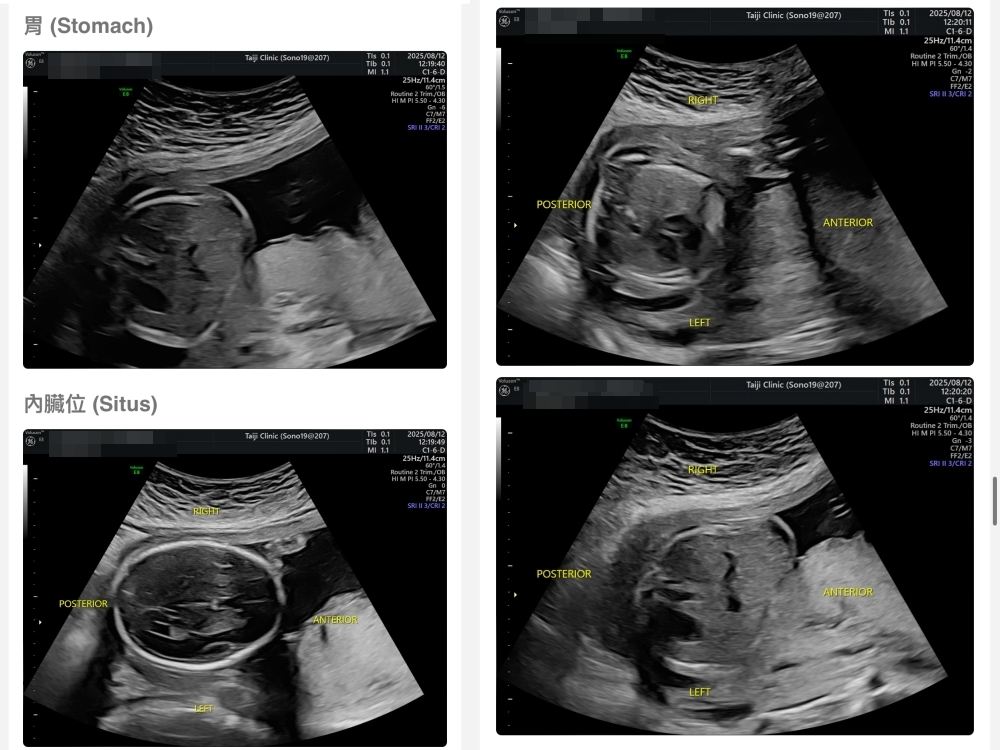

▲離開診所後會收到MAIL,我們14:05離開,大約是16:45收到mail,裡面會有滿滿的超音波照片,紀錄的很詳細!也會提供紙本的報告,可以給日後產檢的醫師做參考👌